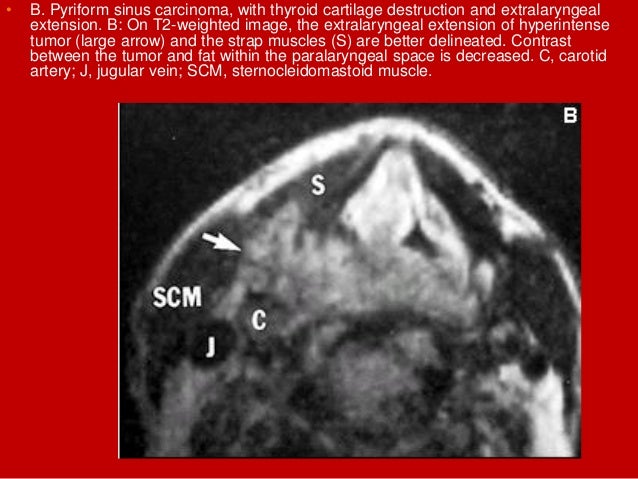

68. 68. • B. Pyriform sinus carcinoma, with thyroid cartilage destruction and extralaryngeal extension. B: On T2-weighted image, the extralaryngeal extension of hyperintense tumor (large arrow) and the strap muscles (S) are better delineated. Contrast between the tumor and fat within the paralaryngeal space is decreased. C, carotid artery; J, jugular vein; SCM, sternocleidomastoid muscle.

69. 69. • B. Pyriform sinus hypopharyngeal squamous cell carcinoma. • a large hypopharyngeal mass (small arrowheads) extending posterolaterally to abut the left carotid artery (c) and displacing the barium filled hypopharynx to the right (arrows). A small left jugular lymph node is noted (large arrowhead).